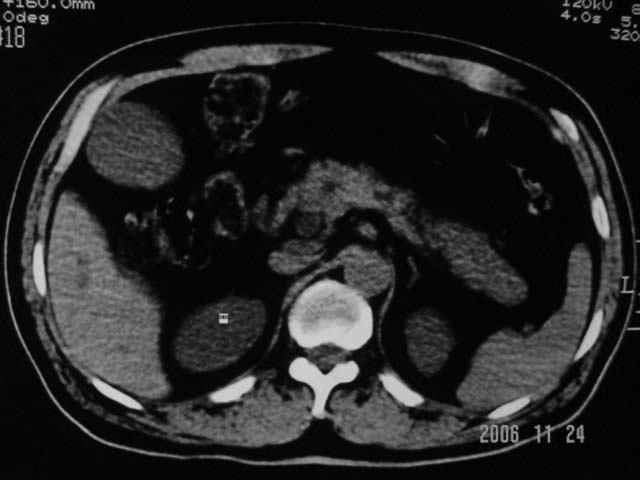

标题: CT5395:男、60岁,皮肤、巩膜黄染伴上腹部疼痛20天 [打印本页]

标题: CT5395:男、60岁,皮肤、巩膜黄染伴上腹部疼痛20天

劳烦各位老师看一下最后一幅箭头指的地方是不是胆总管结石.ct值约63hu.

感觉不是结石可能,与上一层面联系应该是门脉区影像,图像显示不佳,胆总管显示不清[特别是胰头以上段],目前影像只能说肝内外胆管扩张,胰管扩张,胆囊扩大。提示胆总管远端梗阻。可考虑肿瘤或结石所致

请结合临床及进一步检查。

胆总管内结节状高密度灶,边缘隐约可见低密度环绕,首先考虑结石伴肝内胆管扩张; 2、胆囊增大,胆囊炎

不过最好与超声结合或增强扫描

肝内外胆管及胰管均示有扩张,胆囊增大.提示胆总管远端梗阻,可考虑肿瘤或结石或肿瘤伴结石,建议强化扫描

1.肝内外胆管扩张,楼主箭头所示处多系结石.

2.图象太黑,窗位太高,窗宽太窄,解剖结构显示欠佳 .